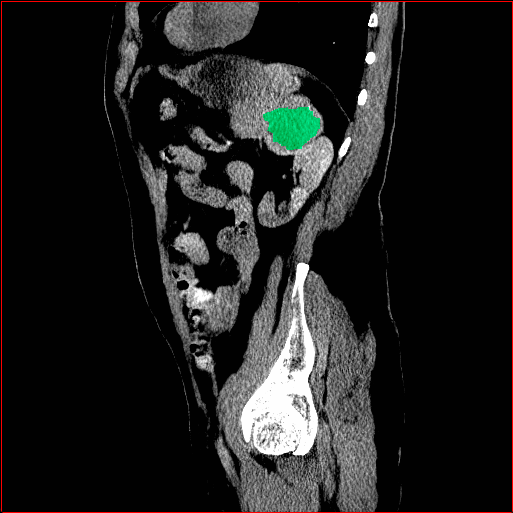

Figure 5 shows qualitative results for MAISI-v2 Controlnet on 5 types of tumors.

Liver Tumor

0.75×0.75×0.50.75\times 0.75\times 0.5

mm

512×512×768512\times 512\times 768

Figure 5: MAISI-v2 segmentation-guided results for five types of tumors. We show results for different voxel spacing and volume size to demonstrate the flexibility of MAISI-v2. Different Hounsfield Unit window is used to better show the contrast between tumor and normal tissues.